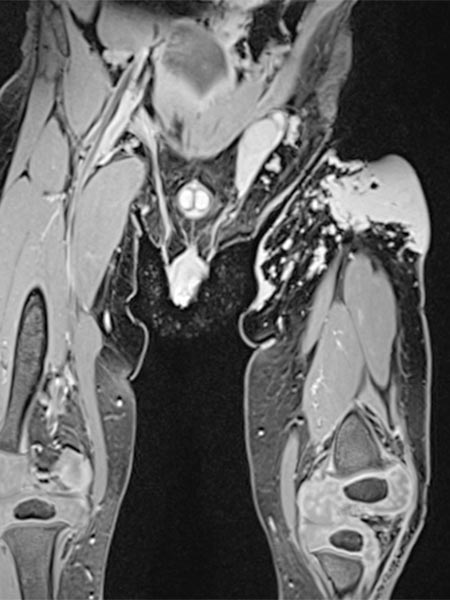

Coronal T2-weighted, fat-saturated MRI shows the tumor in the left groin as homogeneous and highly hyperintense (13 months of age) and clearly solid. Incidental findings include the soaked diaper, also with high signal intensity.

Same MRI sequence, coronal slice. The tumor is not only epifascial, but also shows a small subfascial extension under the fascia lata into the gluteal muscles. Thus, clearly infiltrative behavior.

Axial slice of MRI (T2-weighted, fat-saturated) also clearly shows the infiltration of the musculature by the mass. Hemangiomas as vascular tumors can also exhibit such infiltration without necessarily being malignant.

In non-enhanced coronal T1-weighted MRI, the tumor is isointense to the musculature without containing adipose tissue. Thus, it is hardly distinguishable from the musculature in this sequence.

Axial T2-weighted MRI without fat saturation shows the tumor as homogeneous and only slightly hyperintense. It is more hyperintense than muscle, but overall much less hyperintense than the surrounding subcutaneous adipose tissue.

Coronal T1-weighted, fat-saturated MRI after contrast administration. The tumor shows homogeneous, strong enhancement. Inside it, two flow voids as a sign of strong arterial perfusion.